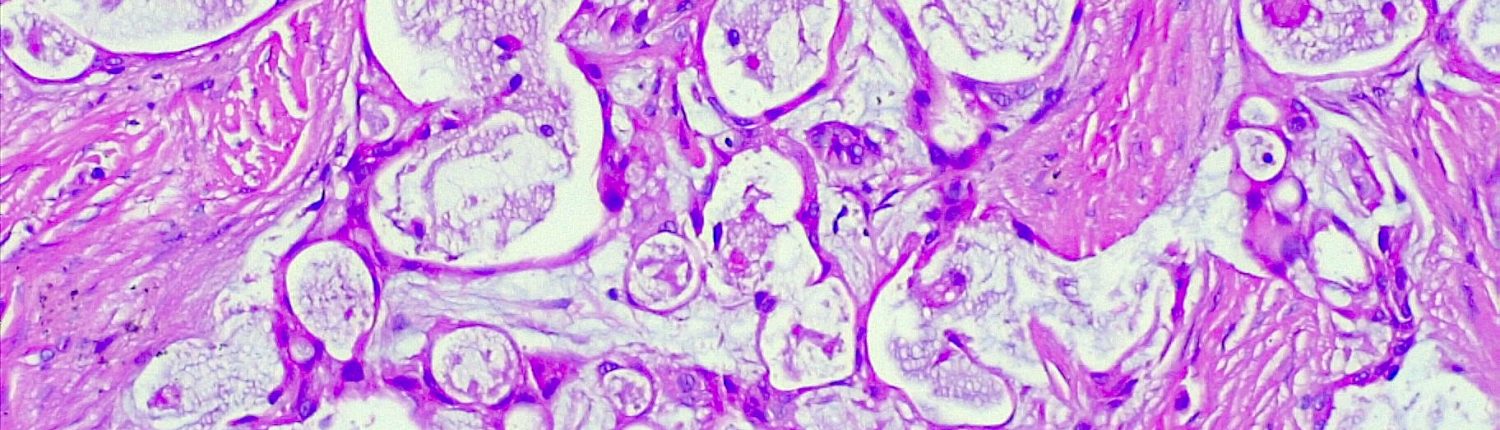

Cirujano Dentista. MSc y PhD en Estomatología y Patología Oral. Profesor de la Universidad de los Andes. Oncología Oral y Medicina Oral.